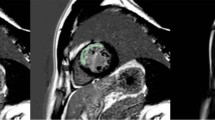

Figure 2 presents a visualization of the scab and two of the top NCA selected features for three patients from different classes to showcase the textures of best predictive features in three different classes.